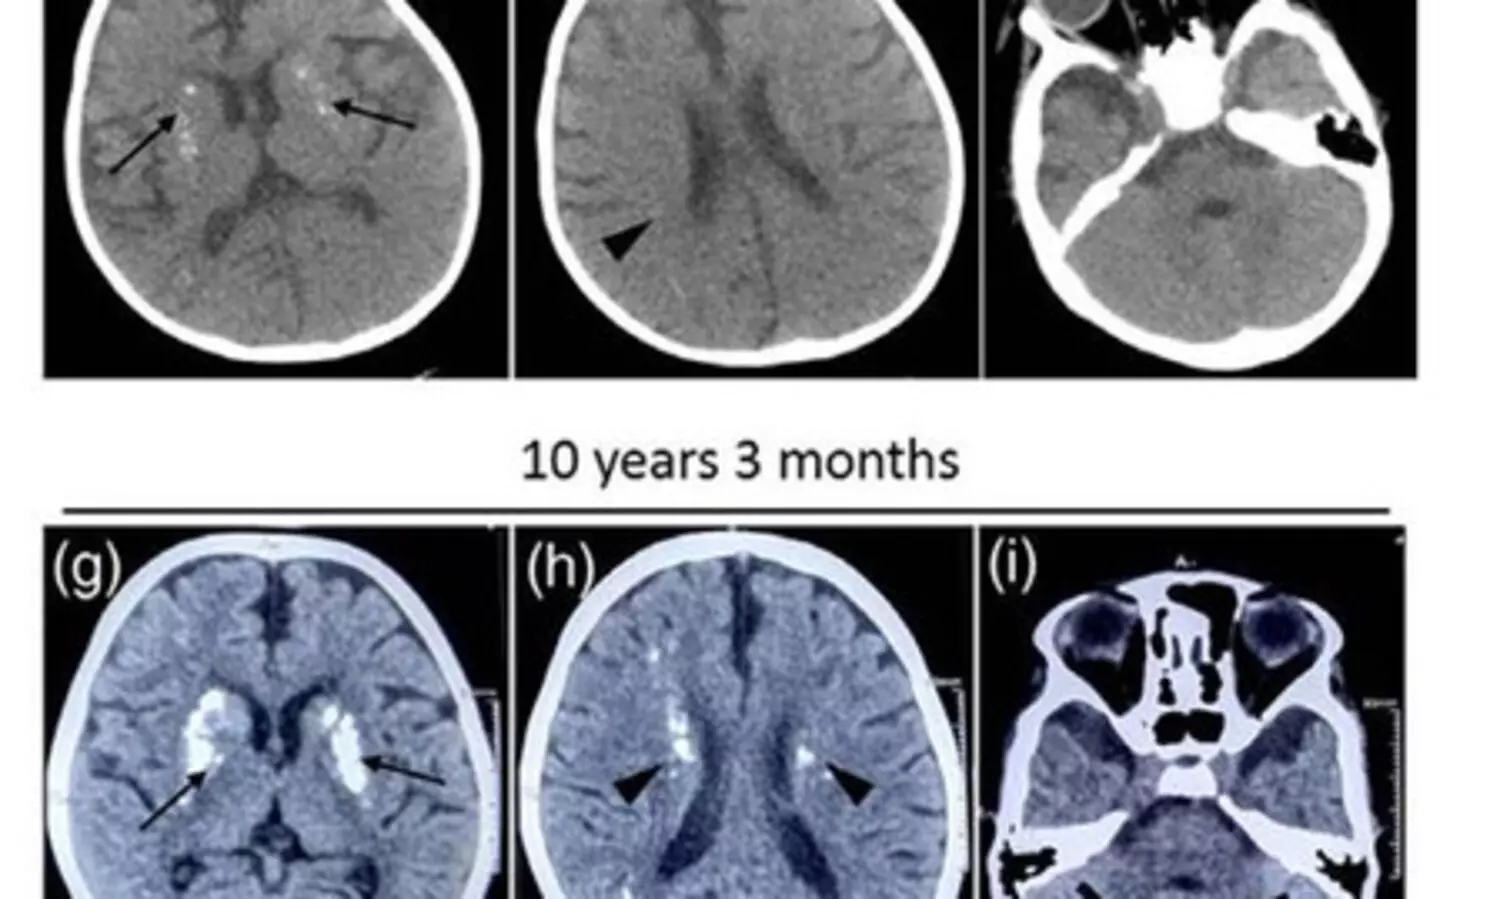

The research was initiated with an 11-year-old girl who began experiencing symptoms from infancy, including repeated episodes of febrile encephalopathy, that is, fever-linked unconsciousness, seizures, delayed development, and a small head size.

Over the years, her scans also showed increasing calcium deposits in different parts of the brain.